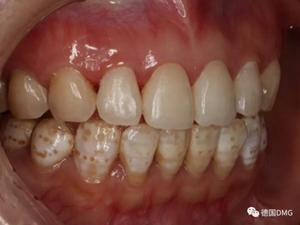

檢查:全口中重度氟斑牙,前牙表面釉質(zhì)白堊色+黃色斑點+凹坑缺損。

1,術前照片,全口氟斑牙,前牙表面釉質(zhì)白堊色+黃色斑點+凹坑缺損。

術前正面?zhèn)让嬲掌?/span>